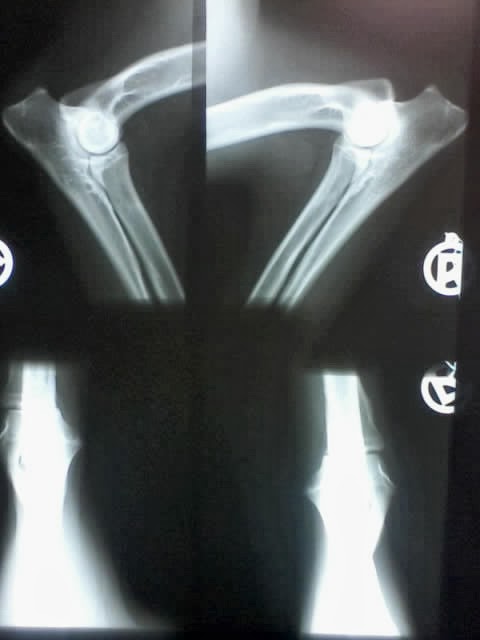

HELLA KUKLIKHD - Frei ED - Frei